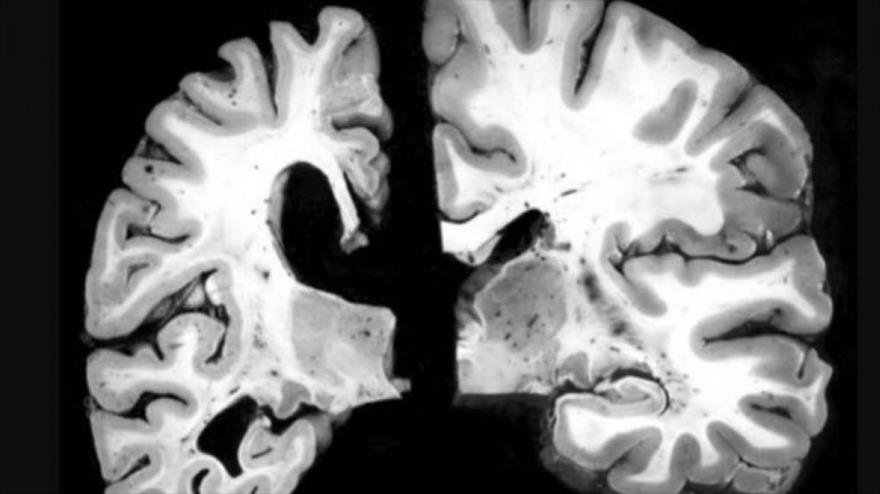

Los científicos también tuvieron acceso a imágenes de resonancia magnética (MRI), que fueron transformadas en algoritmos computarizados para descubrir cambios en la anatomía cerebral.